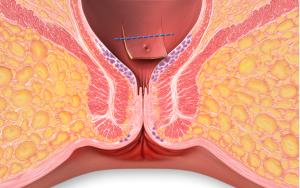

Perianal fistulas are abnormal tracts or “tunnels” between the anal canal or rectum and an external opening in the skin near the anus and are the most common type of fistula in Crohn’s disease. This can be referred to as perianal Crohn’s disease or perianal fistulizing disease. These fistulas can be painful, especially if there is an abscess or infection at the site. They can cause leakage of stool, pus, or blood that you may see on your underwear.

Having surgery can be beneficial in helping a fistula heal and may depend on where your fistula is located. The goal of surgery is to heal the perianal fistula while avoiding damage to anal sphincter muscles as these muscles surround the area and control the elimination of stool. If there is an abscess, a colorectal surgeon trained in management of Crohn’s abscesses and fistulas will surgically drain the abscess.

Setons

Seton placement is one option to help heal perianal fistulas. A seton is a thin rubber surgical thread that is placed through the fistula tract and exits out through the anus. The seton is then tied to form a loop, with the end of the loop hanging out of the anus. This allows the tract to stay open for the fistula to drain which helps avoid infectious complications. The seton is left in for at least several months and then potentially removed once the fistula has drained in some instances. The seton can be removed in the office or in the operating room if it requires additional surgery. After the infection is cleared, medical management to control the inflammation is required to continue healing the fistula tract.